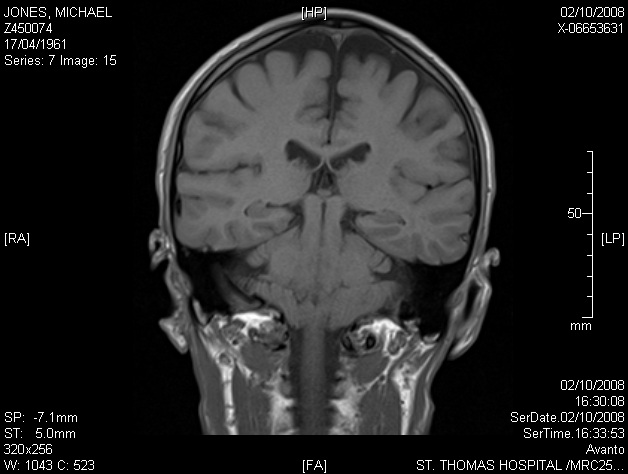

Image 7.15 — final scan image in which this object is visible — approximately 6mm to the rear of 7.14. The object is somewhat narrower and less circular here. It reaches its limit at this point, suggesting it may be 12-15mm in depth.

« 7.14 (full)  |  7.15 (detail x4)